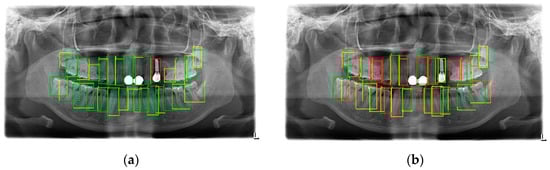

This round of experiments compared the SPSC-NET method with Faster-RCNN, Retina-net, SSD, and SSD-lite methods; it should be noted that our purpose in testing Faster-RCNN was to reproduce the work of Laishram et al. []. At the same time, in order to compare the performance of Faster-RCNN in the original text, we also compared the raw data of Faster-RCNN in the text (the training images was 96, but there was no AP50, AP75 and mIOU in that paper). In addition, to demonstrate the effectiveness of few-shot object detection learning on dental detection tasks, we also reproduced the performance of TFA, including TFA based on full connection and TFA based on cosine similarity. Faster-RCNN, Retina-net, SSD, SSD-lite, and TFA model training adopted the transfer learning method, pre-training on the basis of COCO2017 data set pre-training, and then fine-tuning training on the small-sample tooth object detection training set. In terms of settings, the learning rates of Faster-RCNN, Retina-net, SSD, and SSD-lite were all 0.01, and the steps were 200; multiplied by 0.1, epochs were 800, batch-size was set to 20, and the confidence threshold of the output result of Faster-RCNN was set to 0.5. Since the default confidence threshold was low, at 0.05, there were a lot of duplicate and misclassified prediction boxes. In the hyperparameter setting of TFA, iter was set to 20,000, batch-size was set to 20, and the rest used the default parameters of the original author of TFA. In the SSD and SSD-lite models, the corresponding data enhancement methods of SSD were used, including random image photometric distortion, scaling, mIOU-based cropping, and horizon flipping. Other parameters were the torchvision default values, and the AP value [] was tested after training. Before the AP evaluation, the output format of SPSC-NET needed to be converted. Since the SPSC-NET method outputs some single-object segmentation images instead of bounding boxes, it is necessary to take the four largest coordinate values of the upper, lower, left, and right of the single-segmented image as the object detected box (x1, y1, x2, y2). At the same time, this experiment also designed an ablation experiment comparison; that is, using the object bounding box generation method proposed in this paper and the task of classifying the grayscale image of a single tooth, called SPSC-NET. In the AP test results, the object detection effect of SPSC-NET was much better than that of Faster-RCNN. As shown in Table 4, ft in the table represents fine-tuning, which shows that the object detection ability of SPSC-NET under few-shot was higher, and the ability to cover the object was stronger. The worst performance class in the SPSC-NET method was the 8th class with the smallest sample size. For the precision–recall curve, the precision–recall curve of the 8th class was still sufficient to lead the best performing class of Faster-RCNN, as shown in Figure 15; Figure 15a is the worst category precision–recall curve of this method, and Figure 15b is the best category precision–recall curve when the Faster-RCNN Box score = 0.8.

As shown in Table 4, the object detection ability of SPSC-NET in the case of few-shot was significantly improved compared to Faster-RCNN. The reason for this phenomenon is that SPSC-NET uses images of tooth semantic structure information. The object detection ability of the model in the training process was significantly enhanced, and the SPSC-NET was more powerful in the object classification, due to the use of the tooth object classification method based on the fusion semantic image. Based on the above reasons, the object detection ability of SPSC-NET was better than that of Faster-RCNN. At the same time, we also found that, although the AP value of Faster-RCNN is better when the box score is very low, the performance of its mIOU is even worse. The actual performance of the two is shown in Figure 16: Figure 16a is the output of the SPSC-NET method, and Figure 16b is the output of the Faster-RCNN when the box score is 0.3. Red is the wrong ROI, and green is the correct ROI. From the detection in the figure, although the AP value of Faster-RCNN-based tooth object detection reached 73.56, due to the defects of the AP value, as the number of frames increased, the performance decline did not affect the AP value when the recall value unchanged, and the decrease in the accuracy rate did not affect the AP score, so the actual performance of Faster-RCNN was much worse than the performance on the AP data indicator. According to the results of the work of Laishram et al. [], the Faster-RCNN performance was higher after training with 96 images. This proves that with the same model, the increase in the training image improves the model performance of Faster-RCNN. It is also worth noting that in our comparison, the single-stage object detector based on transfer learning was not of practical value for the performance, which is consistent with the review results of Singh et al. []. In addition, the TFA method in the field of small-sample object detection did not perform well in our tests, which can confirm why there is little research in the field of dental detection using the FSOD method; the reason for this phenomenon is because TFA relies on the base dataset, and using the generic dataset as the base dataset will cause the source domain to mismatch the target domain. Unlike Faster-RCNN, if the researchers want to apply the FSOD method to the field of tooth target detection, they need to conduct more in-depth research on the FSOD models and the feature of tooth detection data.

Figure 16.

Image comparison between (a) SPSC-NET and (b) Faster R-CNN when box score is 0.3.